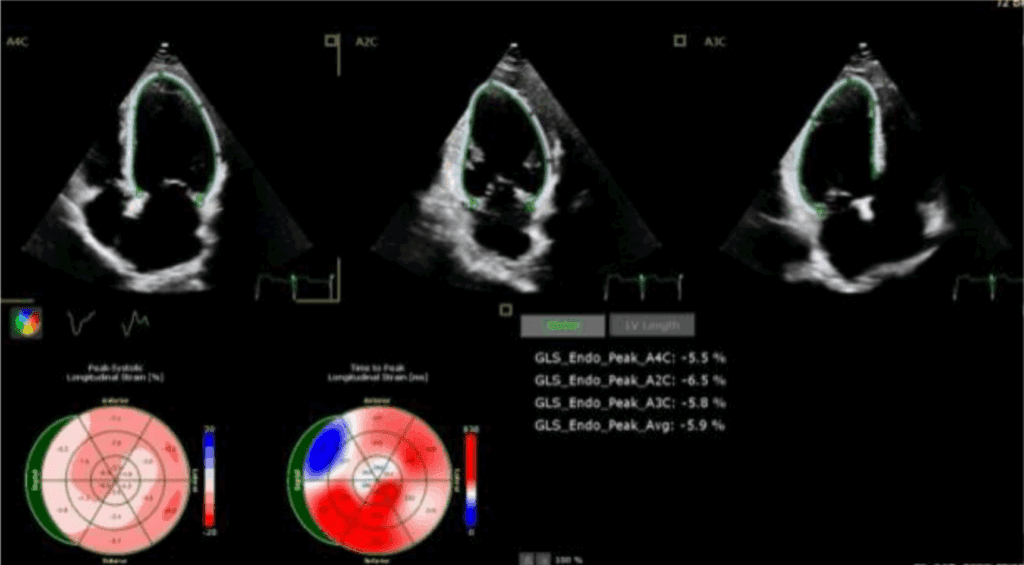

Odkształcenie mięśnia sercowego (strain) jest metodą diagnostyczną oraz coraz lepiej udokumentowanym parametrem prognostycznym, który uzupełnia standardowe przezklatkowe badanie echokardiograficzne (ang. transthoracic echocardiography – TTE).